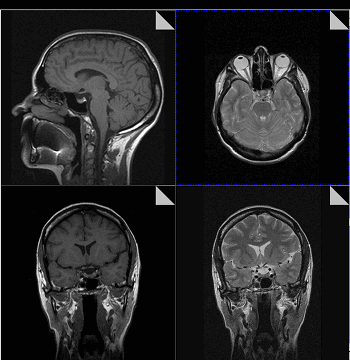

Что показывает МРТ

Магнитно-резонансная томография или МРТ - это сфокусированный метод, который проводит очень детальное обследование. Диагностическая точность МРТ превышает УЗИ и во многих случаях КТ, за исключением сканирования полых органов (легких, желудка, кишечника) и костей. МРТ является золотым стандартом диагностики:

- заболеваний головного и спинного мозга;

- патологий суставов;

- межпозвоночных дисков;

- сердца и сосудов;

- болезней гинекологического, проктологического и урологического характера.

В отличие от быстрого КТ и УЗИ, магнитно-резонансное обследование требует времени - в среднем пациенту нужно лежать в томографе и соблюдать неподвижность 30-60 минут.

Принцип работы МРТ основан на эффекте ядерного магнитного резонанса. МР томограф в своей конструкции имеет мощный магнит, который создает магнитное поле, и датчик, который подает радиочастотные сигналы. В такой ситуации протоны атомов водорода начинают колебательные движения, выделяя при этом импульсы. Их улавливает компьютер томографа и преобразовывает в трехмерные изображения. Чем больше воды содержится в клетках ткани, тем детальней получается ее изображение. Поэтому на МРТ хорошо отображаются органы с большим содержанием воды: МРТ головного мозга, МРТ спинного мозга, МРТ глазных орбит, МРТ органов малого таза, МРТ позвоночника, МРТ суставов, и плохо визуализируются органы с большим содержанием воздуха МРТ органов грудной клетки или кости.

Существенное преимущество МР-томографии перед КТ заключается в том, что она не противопоказана беременным во II и III триместре и совершенно безопасна для детей. В МРТ исследуемая область сканируется в трех проекциях, что позволяет врачу-рентгенологу в полной мере оценить состояние тканей и органов исследуемой области, а высокая контрастность изображения и пространственное разрешение позволяют визуализировать серое и белое вещество головного мозга, оценивать состояние костного мозга и мягких тканей различной локализации. Кроме того, метод МРТ позволяет получать изображения сосудов головного мозга и сосудов шеи без введения контрастного препарата.